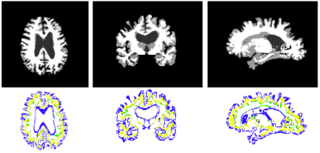

Results from the new implementation are:

Design ITK classes for Hierarchical Attribute Matching Mechanism for Elastic Registration (HAMMER) and White Matter Lesion segmentation so that these algorithms can be easily implemented using the Insight Toolkit and integrated into Slicer. The goals of the week is to analyze the algorithms on the object level, map components to existing ITK classes, identify gaps, and start implementation. Will also identify testing dataset and generate baseline results for testing.

- HAMMER attribute vector computation has been implemented as an ITK Filter.

- Feature point selection has been implemented.

- Feature similarity computation has been implemented.

- HAMMER Registration is been implemented using ITK Finite Difference framework--itk::HammerDeformableRegistrationFunction and itk::HammerDeformableRegistrationFilter.